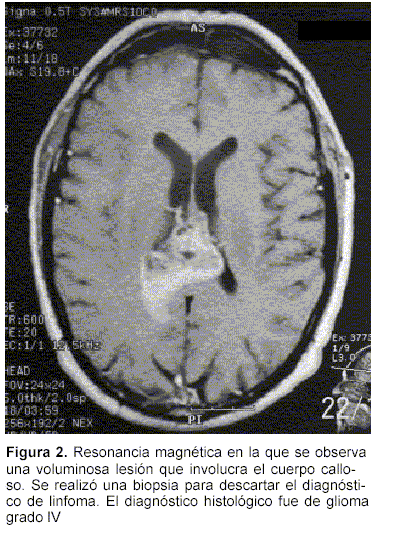

a) Tumores: en 11 casos se diagnosticaron gliomas de alto grado (III y IV). De estos pacientes, dos fueron operados posteriormente para resecar el tumor. En el primer caso se trataba de una lesión hipodensa frontal derecha. La imagenología planteaba la duda entre proceso inflamatorio o tumoral (figura 1). La biopsia determinó que se trataba de un glioma grado III. Luego de la resección quirúrgica fue sometido a radioterapia. Ha tenido una sobrevida de dos años sin secuelas invalidantes. En el segundo caso era una lesión parieto rolándica izquierda de unos 3 cm de diámetro. El diagnóstico fue también de glioma grado III. Se realizó una craneotomía y se resecó la lesión, la que se localizó siguiendo la diéresis cortical realizada para la biopsia. No agregó focalidad neurológica luego de la cirugía. Al momento de escribir este reporte está recibiendo tratamiento radiante. En los restantes casos los tumores eran de topografía gangliobasal o de cuerpo calloso (figura 2), y se consideraron fuera de las posibilidades terapéuticas. Se realizaron biopsias para descartar el diagnóstico de linfoma, tratable con quimioterapia.